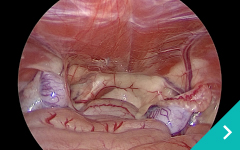

ミニマム創内視鏡下手術は腹腔鏡だけでは対処ができないような手術の際に、お腹にラッププロテクターという器具を設置して行う腹腔鏡と開腹手術を組み合わせた手術です。